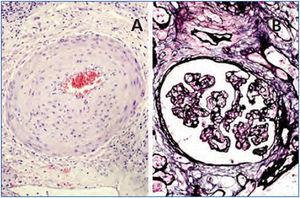

Un varón de 48 años, de raza caucásica, con IRC secundaria a hipoplasia renal, inició hemodiálisis en 1984. Ese mismo año recibió su primer trasplante renal de donante vivo, su padre, que mantuvo funcionante hasta 1997, cuando retornó a hemodiálisis por nefropatía crónica del injerto y se realizó trasplantectomía. En 1999, recibió su segundo trasplante renal de donante cadáver, retornando a hemodiálisis en noviembre de 2002 tras el desarrollo de una glomerulonefritis membranoproliferativa secundaria al VHC sobre el injerto renal. Una hepatitis «no-A, no-B» se diagnosticó en 1984 y una biopsia hepática en el año 2000 mostró una hepatitis crónica periportal (P3L3F2) con RNA de VHC positivo (genotipo 3). Tras el retorno del paciente a hemodiálisis para ser incluido nuevamente en la lista de trasplante renal, se inició en marzo de 2003 tratamiento con IFN-α, 3 millones de unidades tres veces por semana. En abril de 2003 comenzó con dolor a nivel del injerto renal, hematuria y fiebre, por lo que se suspendió el INF-α y se realizó una trasplantectomía programada, observándose en la histología intensas lesiones parenquimatosas de rechazo agudo y crónico (figura 1, figura 2 y figura 3). En agosto de ese mismo año, se confirmó la negativización del RNA-VHC a pesar de haber recibido un mes de tratamiento antiviral. Sin embargo, en enero de 2004 presentó una recidiva, por lo que se reintrodujo el tratamiento antiviral, que se mantuvo durante 12 meses, consiguiéndose una RVS sin nueva recidiva. En febrero de 2008 recibió su tercer trasplante renal de donante cadáver. En la actualidad presenta una función renal normal y mantiene carga viral indetectable cinco años después de la finalización del tratamiento.

Figura 1. Panorámica de rechazo agudo y crónico.

Figura 2. Rechazo agudo.

Figura 3. Rechazo crónico.